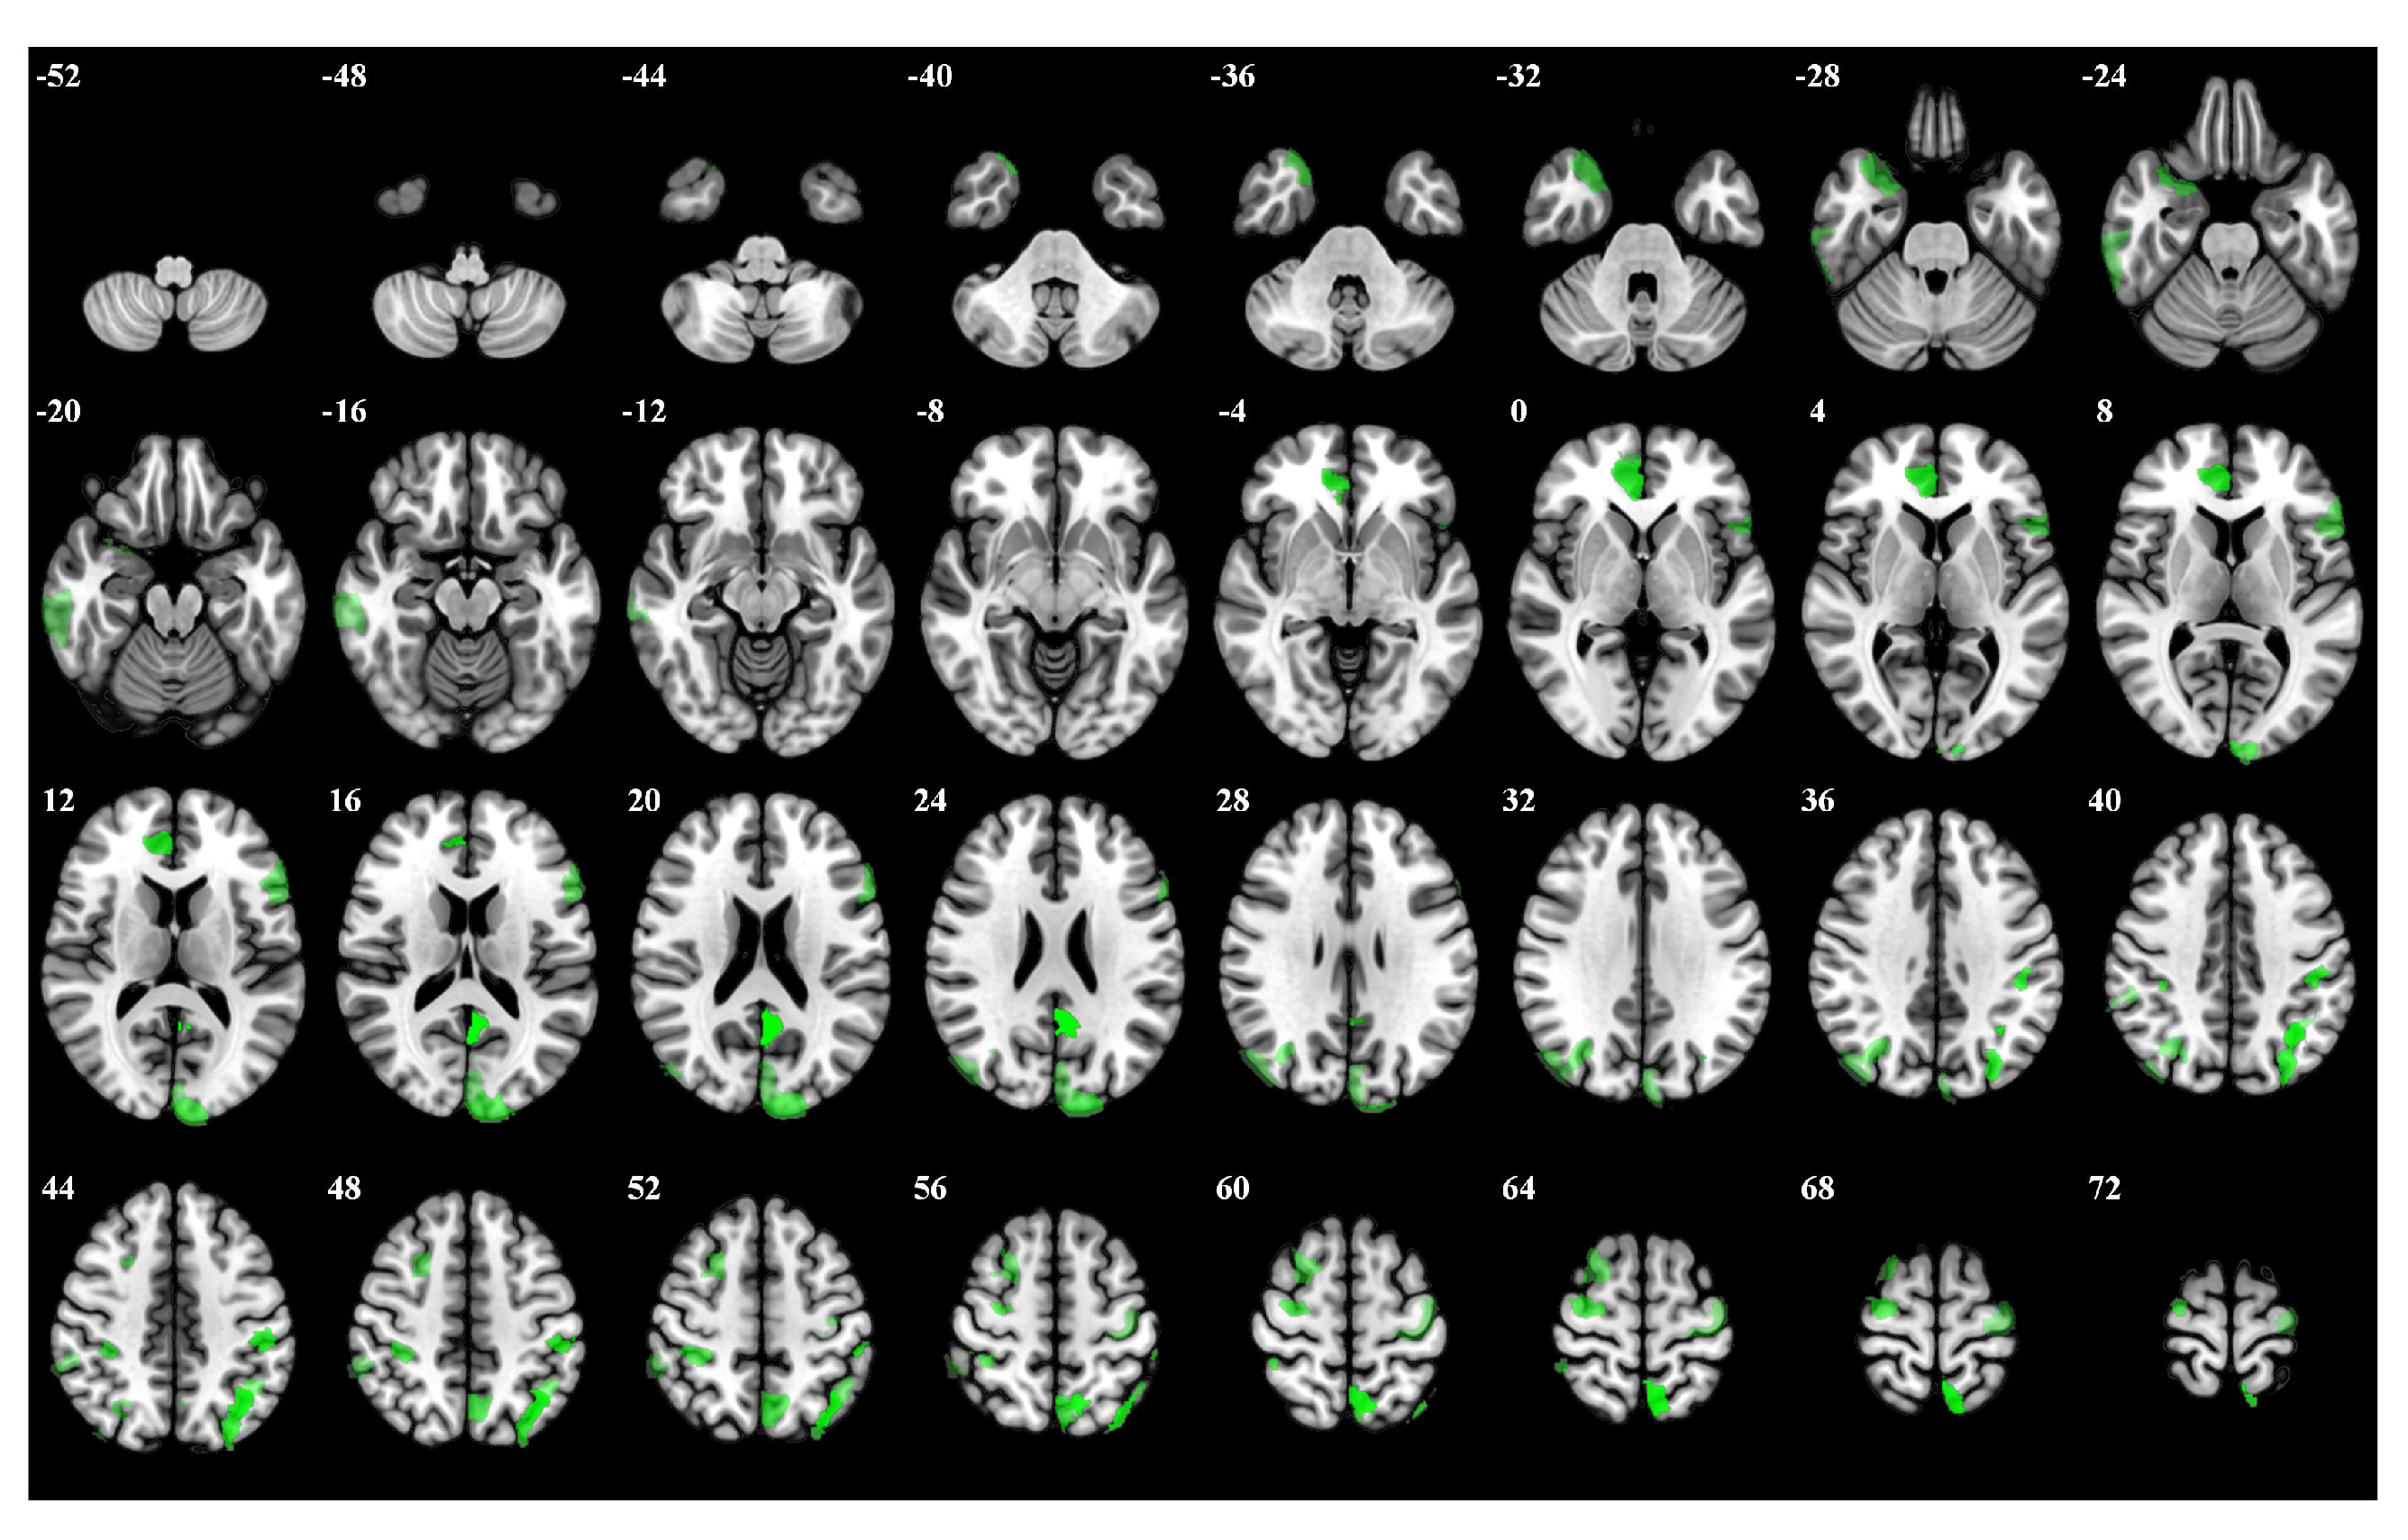

| Rank | Brain Regions | Side | Centroid Coordinates (R A S) | Importance Weight |

|---|---|---|---|---|

| 1 | Default Precuneus Posterior Cingulate Cortex 3 | L | −4 −53 20 | 0.246 |

| 2 | Frontoparietal Control Parietal 4 | L | −35 −62 48 | 0.241 |

| 3 | Dorsal Attention Posterior 15 | L | −7 −59 63 | 0.237 |

| 4 | Limbic Temporal Pole 2 | L | 7 42 4 | 0.216 |

| 5 | Dorsal Attention Posterior 8 | L | −46 −29 44 | 0.212 |

| 6 | Frontoparietal Control Parietal 1 | L | −29 −74 42 | 0.211 |

| 7 | Somatomotor 31 | R | 29 −11 65 | 0.206 |

| 8 | Visual 24 | L | −11 −97 17 | 0.195 |

| 9 | Frontoparietal Control Precuneus 2 | L | −5 −64 52 | 0.187 |

| 10 | Dorsal Attention Posterior 13 | R | 35 −36 51 | 0.181 |

| 11 | Limbic Temporal Pole 5 | R | 29 12 −30 | 0.176 |

| 12 | Frontoparietal Control Parietal 5 | L | −42 −52 49 | 0.174 |

| 13 | Dorsal Attention Posterior 5 | R | 32 −66 35 | 0.171 |

| 14 | Default Prefrontal Cortex 10 | L | −53 19 11 | 0.169 |

| 15 | Frontoparietal Control Lateral Prefrontal Cortex 15 | R | 24 10 58 | 0.165 |

| 16 | Frontoparietal Control Temporal 1 | R | 62 −28 −20 | 0.163 |

| 17 | Somatomotor 26 | L | −36 −19 65 | 0.161 |

| 18 | Visual 25 | L | −3 −84 24 | 0.159 |

| 19 | Dorsal Attention Posterior 4 | R | 45 −75 31 | 0.157 |

| 20 | Frontoparietal Control Parietal 2 | R | 56 −41 48 | 0.153 |